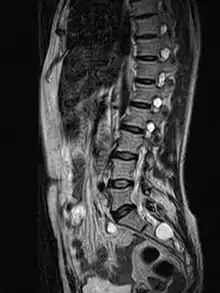

![]() | |

| MRI image showing a Tarlov cyst | |

MRI, or Magnetic Resonance Imaging, is considered the imaging study of choice in identifying Tarlov cysts. MRI provides better resolution of tissue density, absence of bone interference, multiplanar capabilities, and is noninvasive. Plain films may show bony erosion of the spinal canal or of the sacral foramina. On MRI pictures, the signal is the same as the CSF one.